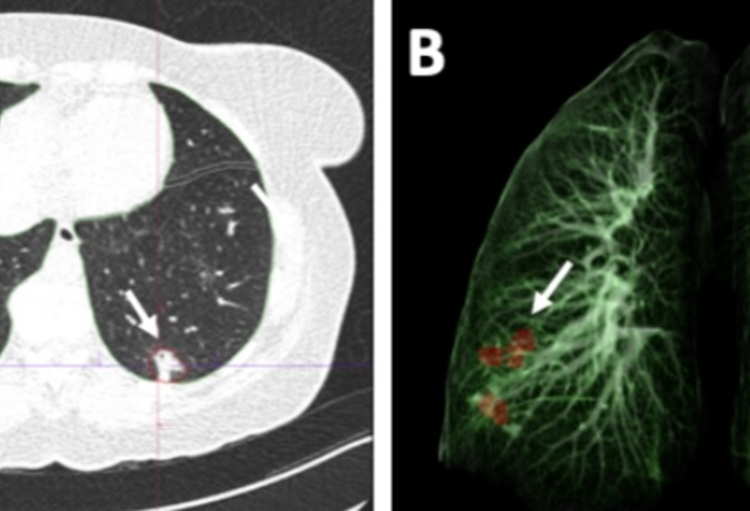

A: CT scan van de longen. De AI software duidt de aangetaste longsegmenten aan (pijlen). B: 3D reconstructie van de longen toont visueel de aangetaste longsegmenten.